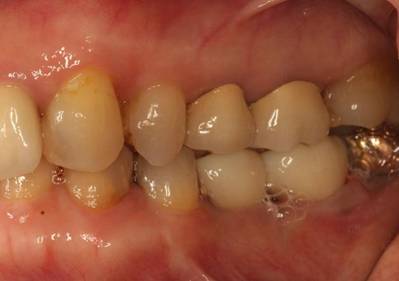

歯周病で抜歯せざるを得ず、インプラントを希望されたケース(使用インプラントはスプライン)

術前。すべての歯が歯周病の末期状態でブリッジ全体がうごいて噛めないとの訴え。右上の犬歯が腫れていました

固定式のブリッジが入っていましたが歯周病で動いています

6年後。犬歯にコンポジット充填。第一大臼歯はメタルボンドになりました

8年後メタルボンド、反対側はジルコニアクラウン